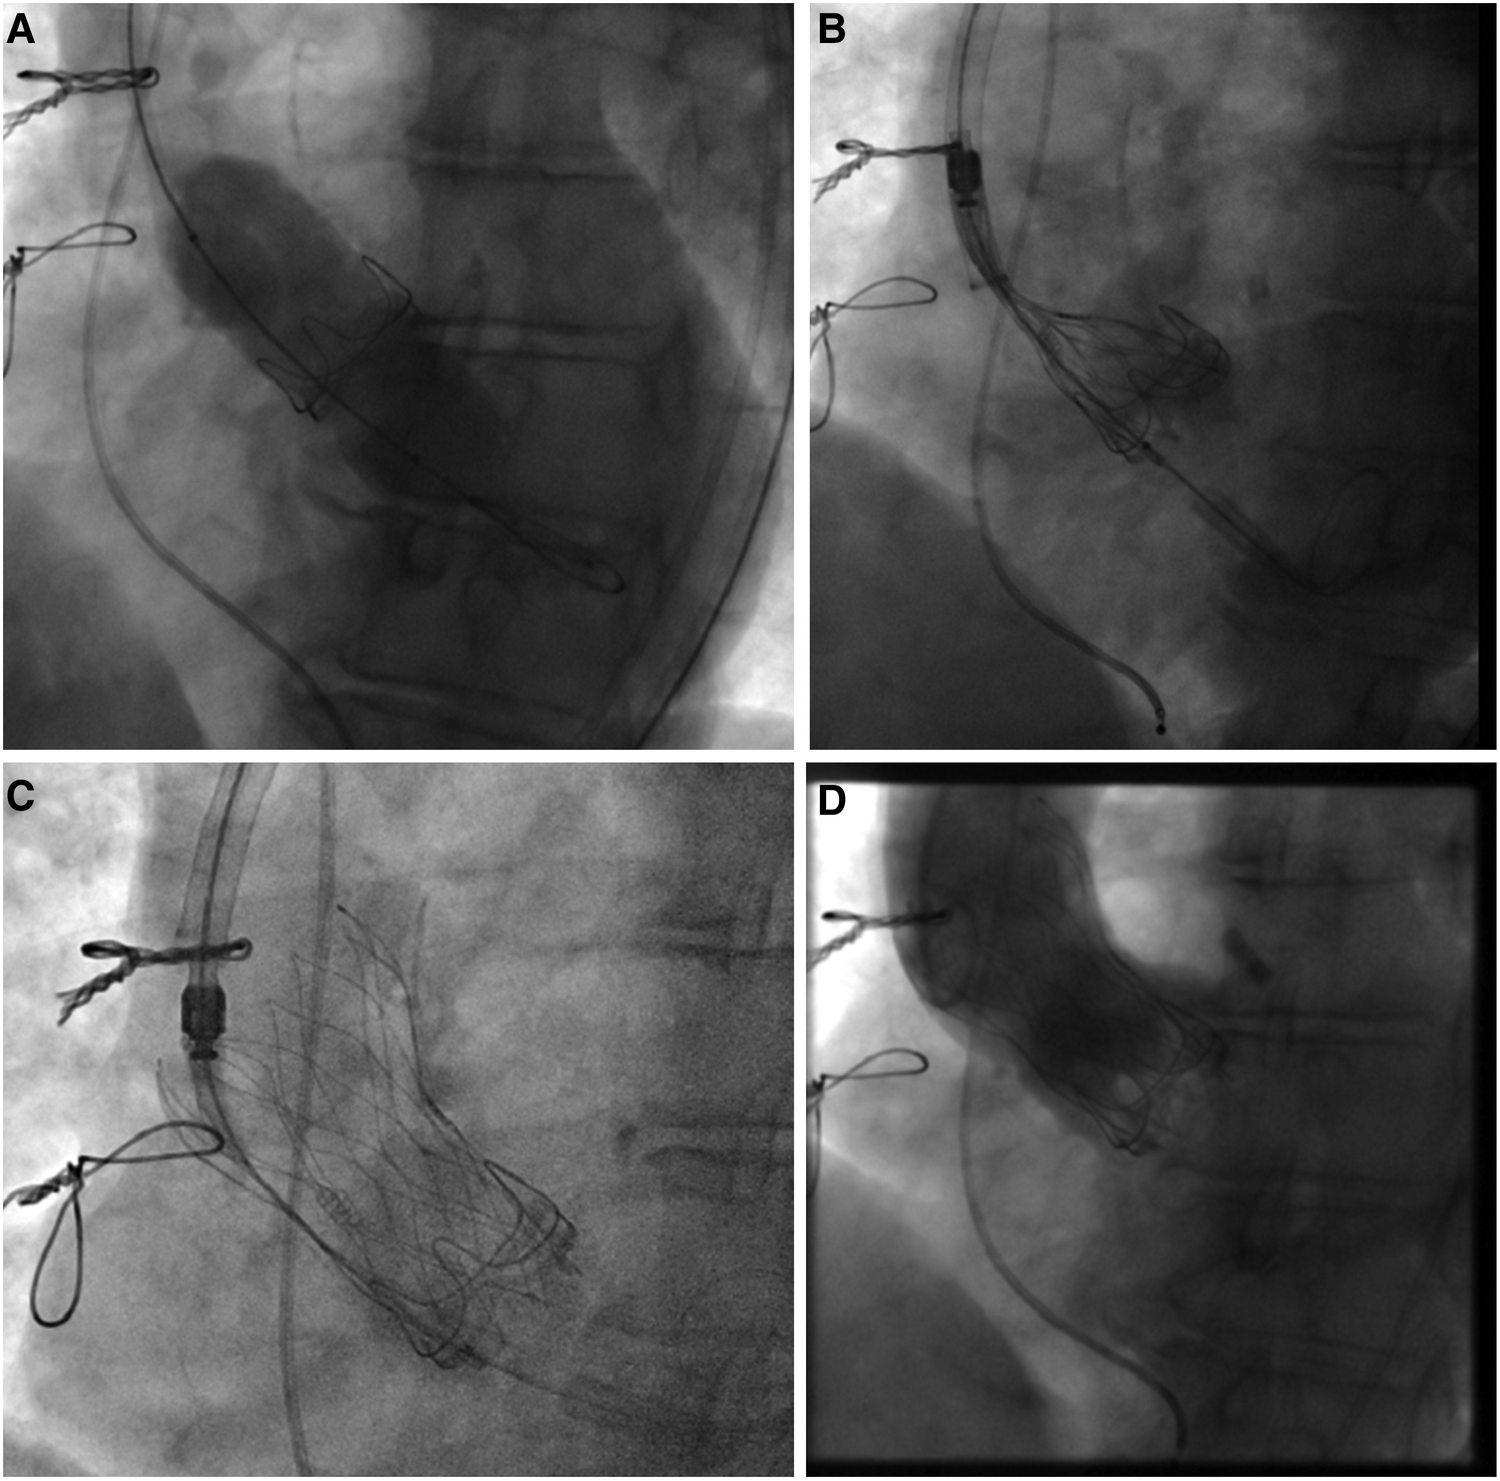

Figure 1

Valve-in-valve procedure using a self-expanding intra-annular transcatheter heart valve for treatment of a failing bovine surgical bioprosthesis. (A) Bioprosthetic valve fracture of a 21 mm (True ID: 19 mm) Perimount surgical bioprosthesis using a 22 mm True Dilatation Balloon. (B) Placement of a 23 mm self-expanding intra-annular transcatheter heart valve into the surgical bioprosthesis and alignment of both stent inflows. (C) Final position with (D) absence of any paravalvular leakage.